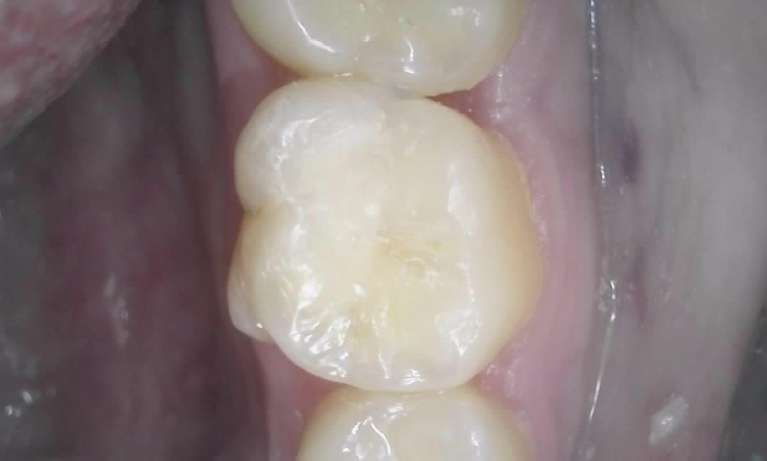

We take great pride in the services we perform in our office. We always try to not only meet your expectations, but we also try to exceed them. There are many types of services that we perform in our office, as well as others that we perform in coordination with highly skilled specialists. We have compiled a few examples of the treatments that we have performed. We are proud to say that these are the usual results our patients expect to see.

The photos are not retouched, nor are they taken by a professional photographer. These are just the routine treatment photos that we take and the results that we see every day. They are by no means a comprehensive catalog of the procedures that we perform. They are just a small sample of some of the results you can expect when you seek treatment in our office.